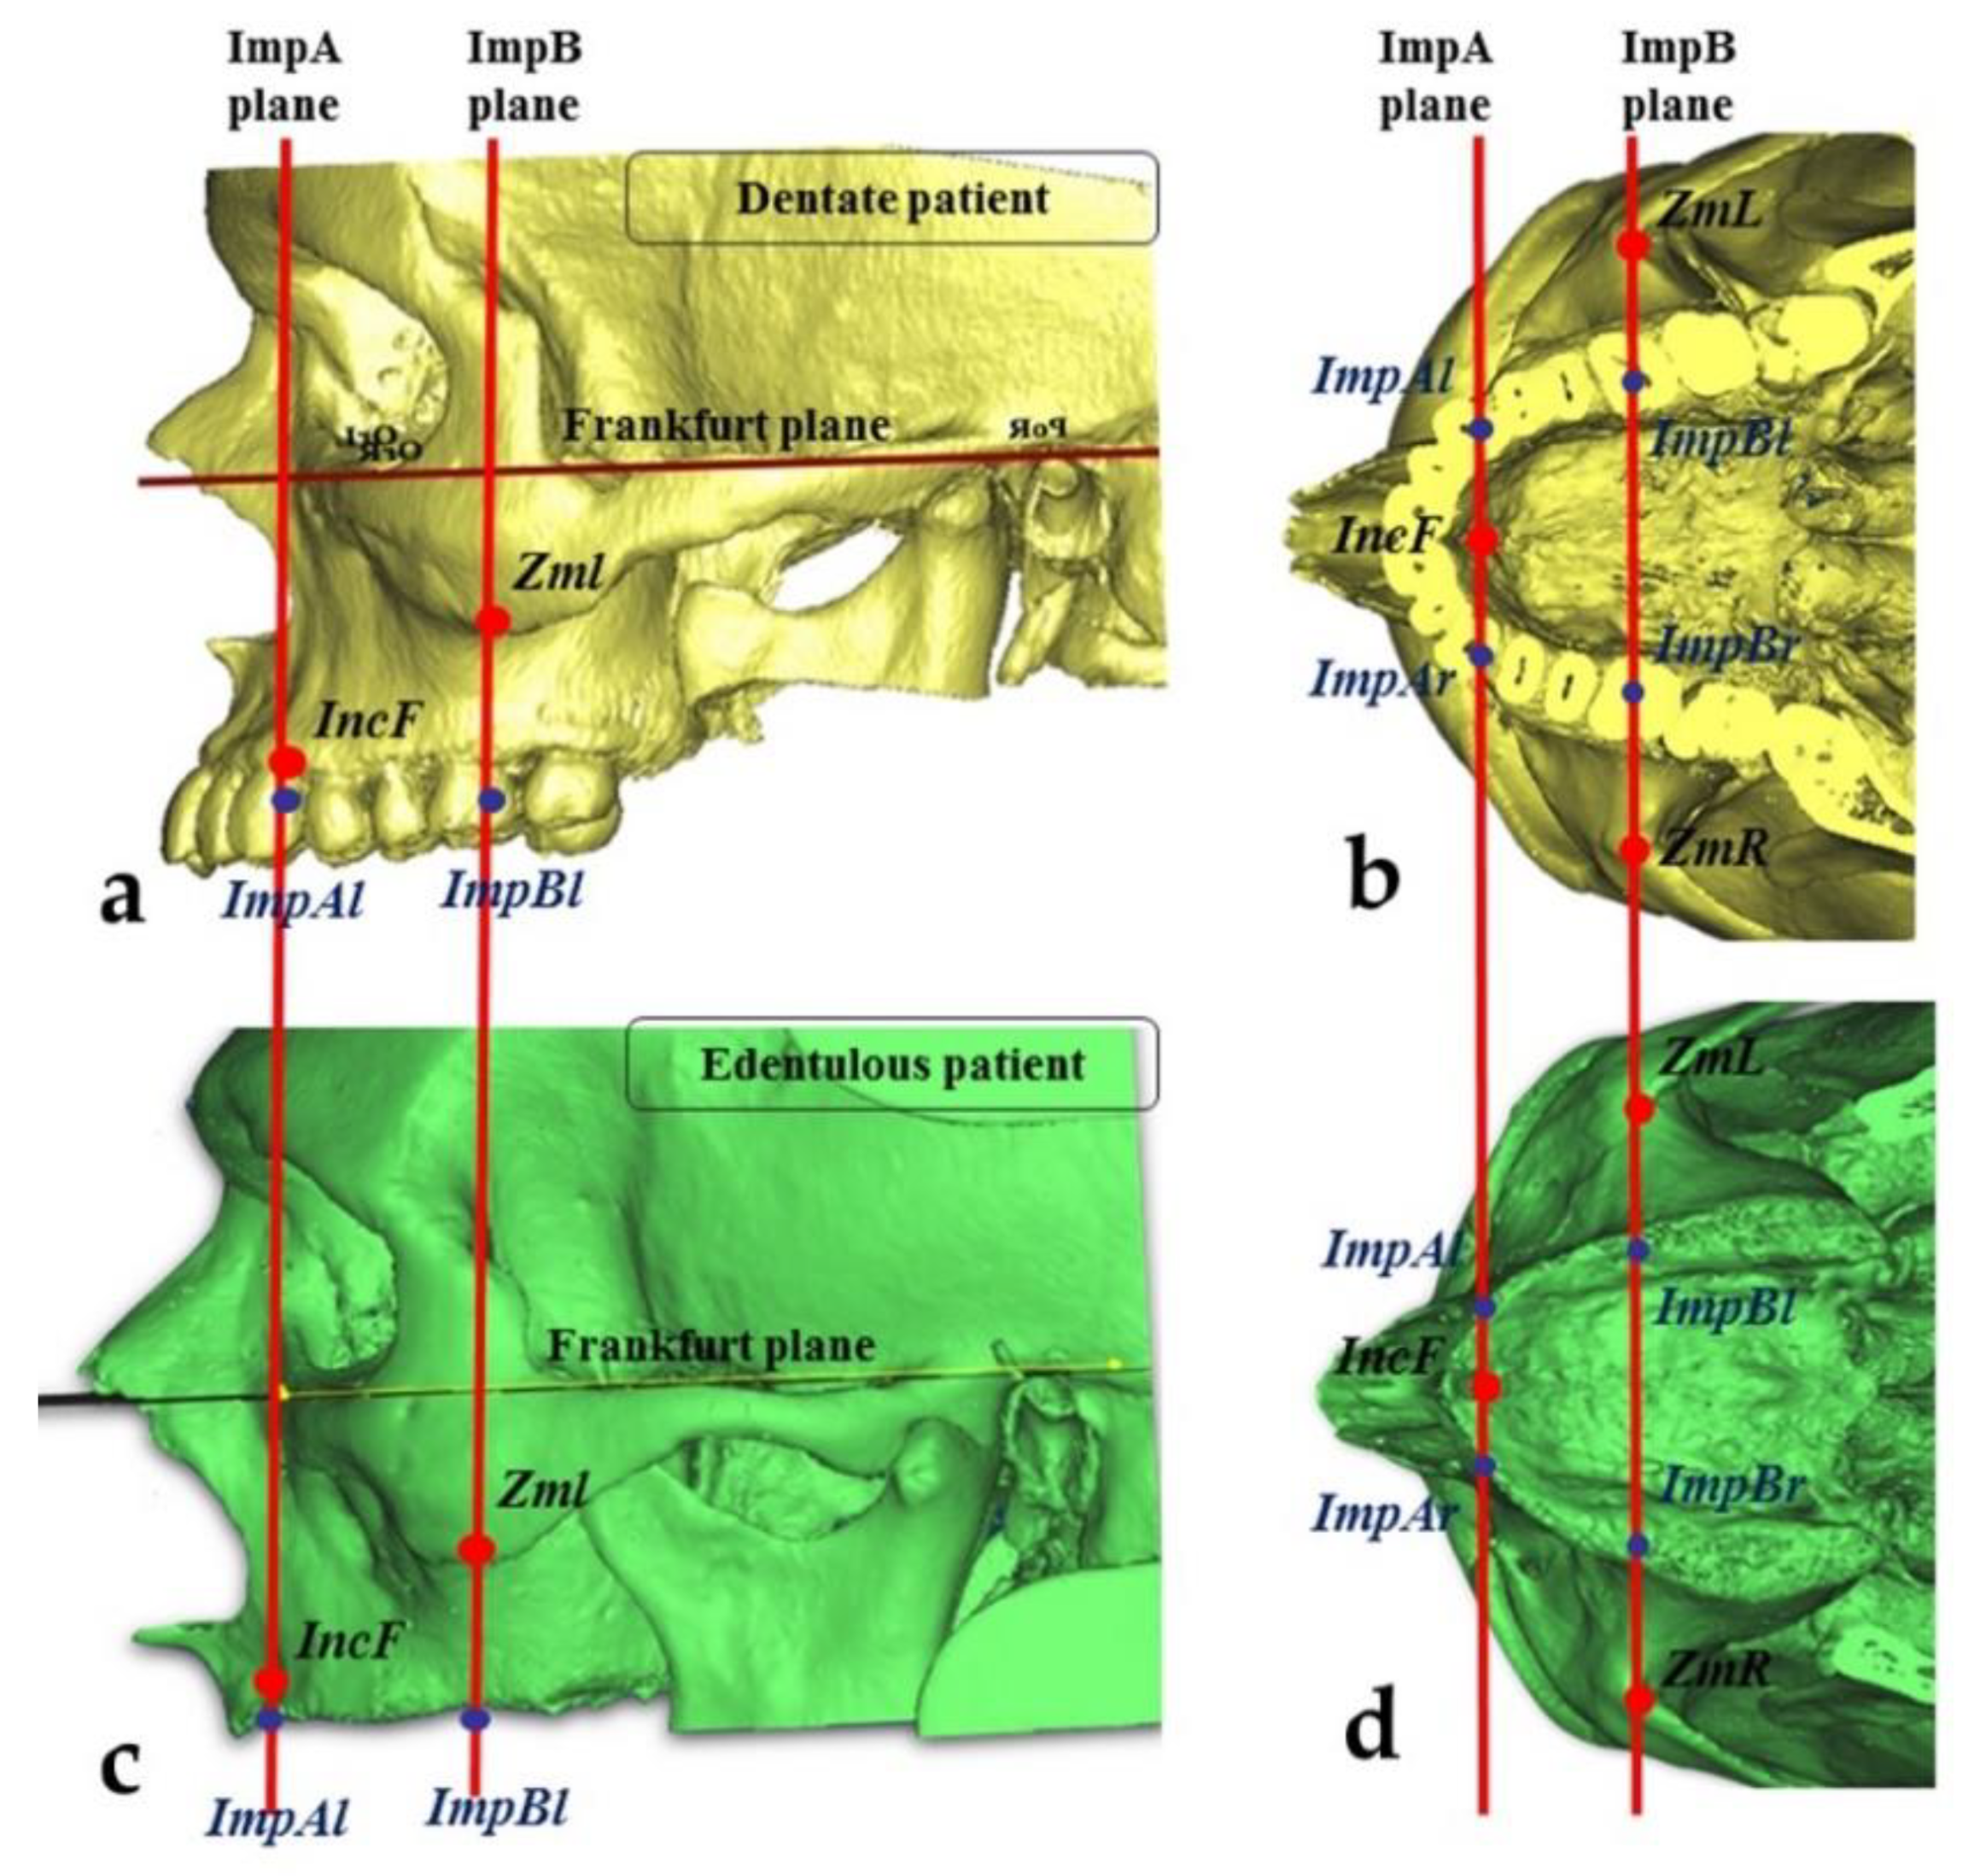

2.3. Measurements of the Zygomatic Bone

- The “upper jugale”: the highest point of the posterior frontal process eminence of the zygomatic bone

- The posterior point of the frontozygomatic suture.Two planes were drawn using the “CAD Objects” tool:

- -

- The “zygomatic anterior” plane, showing the ideal emergence points of prosthetic anterior implants; these were ImpAr/ImpAl and the upper jugale.

- -

- The “zygomatic posterior” plane, showing the ideal emergence points of prosthetic posterior implants; these were ImpBr/ImpBl and the posterior point of the frontozygomatic suture.